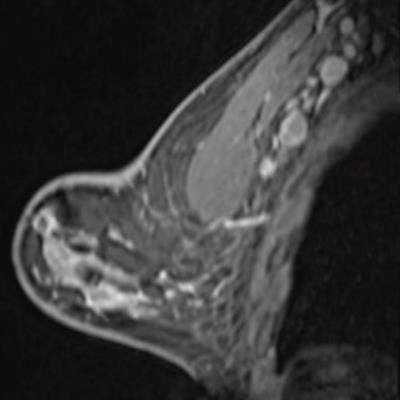

But even with fewer stories overall about COVID-19 in our top 10 ranking, one article about how the vaccine for the disease appeared to be affecting breast imaging results -- particularly manifesting as swollen lymph nodes -- still took first place. Our two other top 10 COVID-19 articles addressed the same topic.

- COVID-19 vaccine affects imaging results, researchers warn

Our number one story posted in February, just as the vaccine rollout for COVID-19 began to ramp up. Two studies published February 24 -- one in the Journal of the American College of Radiology and another in Radiology -- found that effects from the vaccine could manifest on breast imaging in ways that might appear to be disease.

- Swollen lymph nodes after vaccination? Fear not

A story that described the perspective of Israeli researchers on how to make sense of swollen lymph nodes found in breast imaging patients after COVID-19 vaccination, took seventh place on our list. The team stressed that "the reassuring feature of this radiological phenomenon is that it is self-regressing."

- Ultrasound shows lymph node changes after COVID-19 vaccine

In fact, concern about the effects of the COVID-19 vaccine on breast imaging began in January, when radiologists from NewYork-Presbyterian published results in the journal Clinical Imaging from four case studies that showed lymph node enlargement on breast ultrasound.